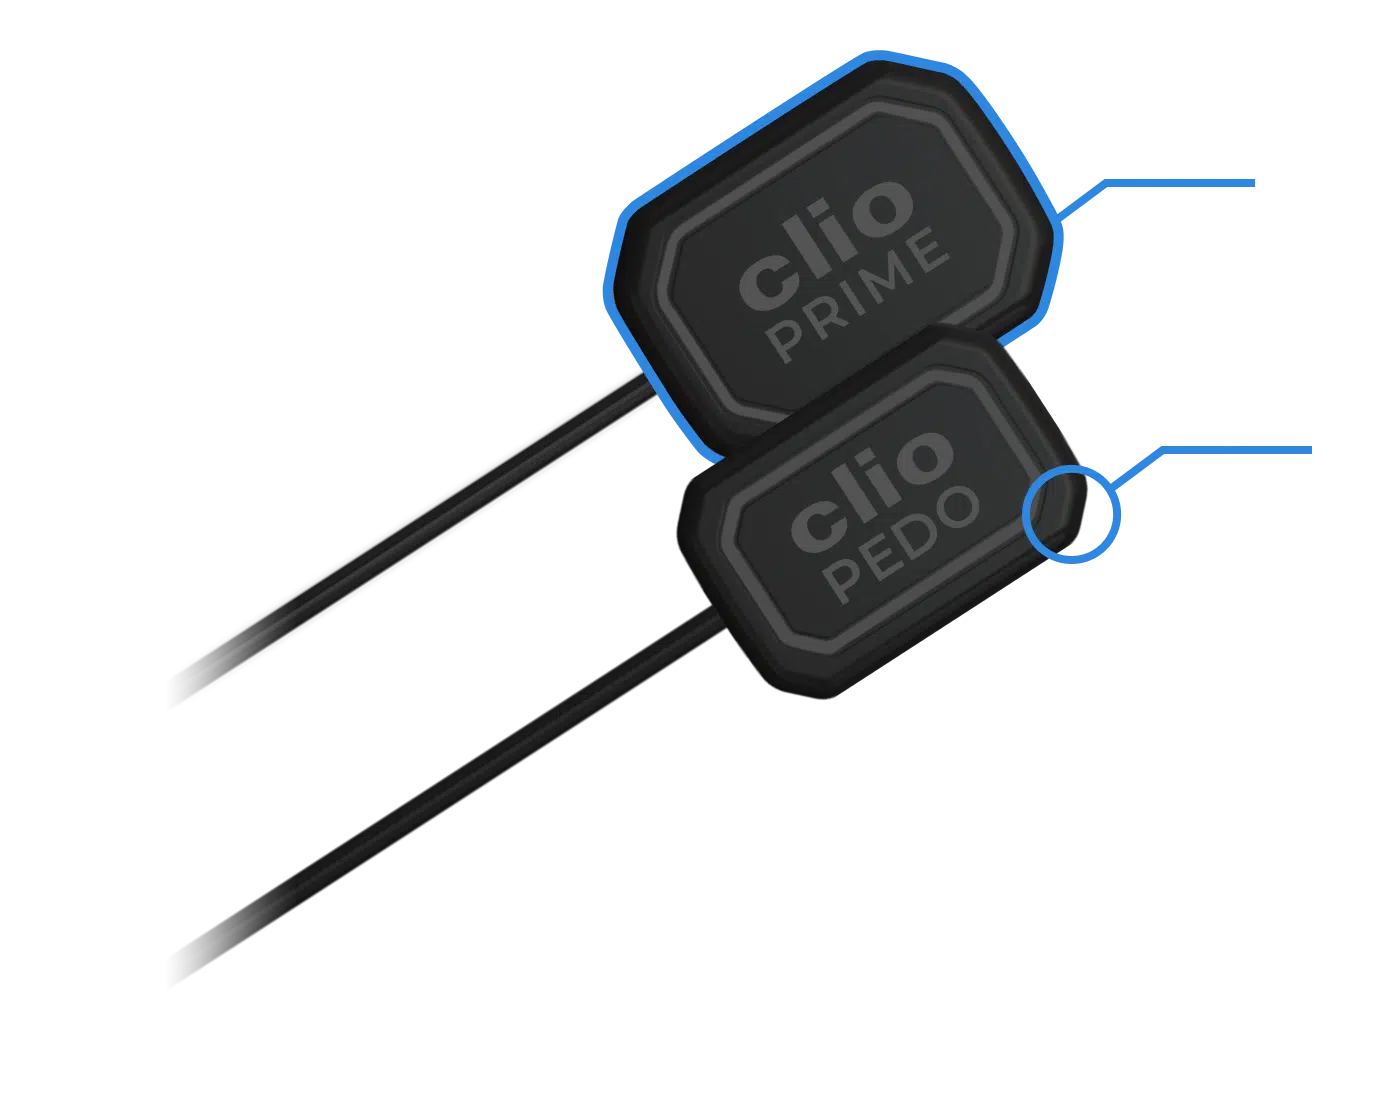

Digital X-Ray Sensor

Clio Prime

The elite digital x-ray sensor with EveryShot X-Ray Capture technology. Eliminates under and overexposure, works with any handheld or wall mount x-ray unit. Made in the USA.